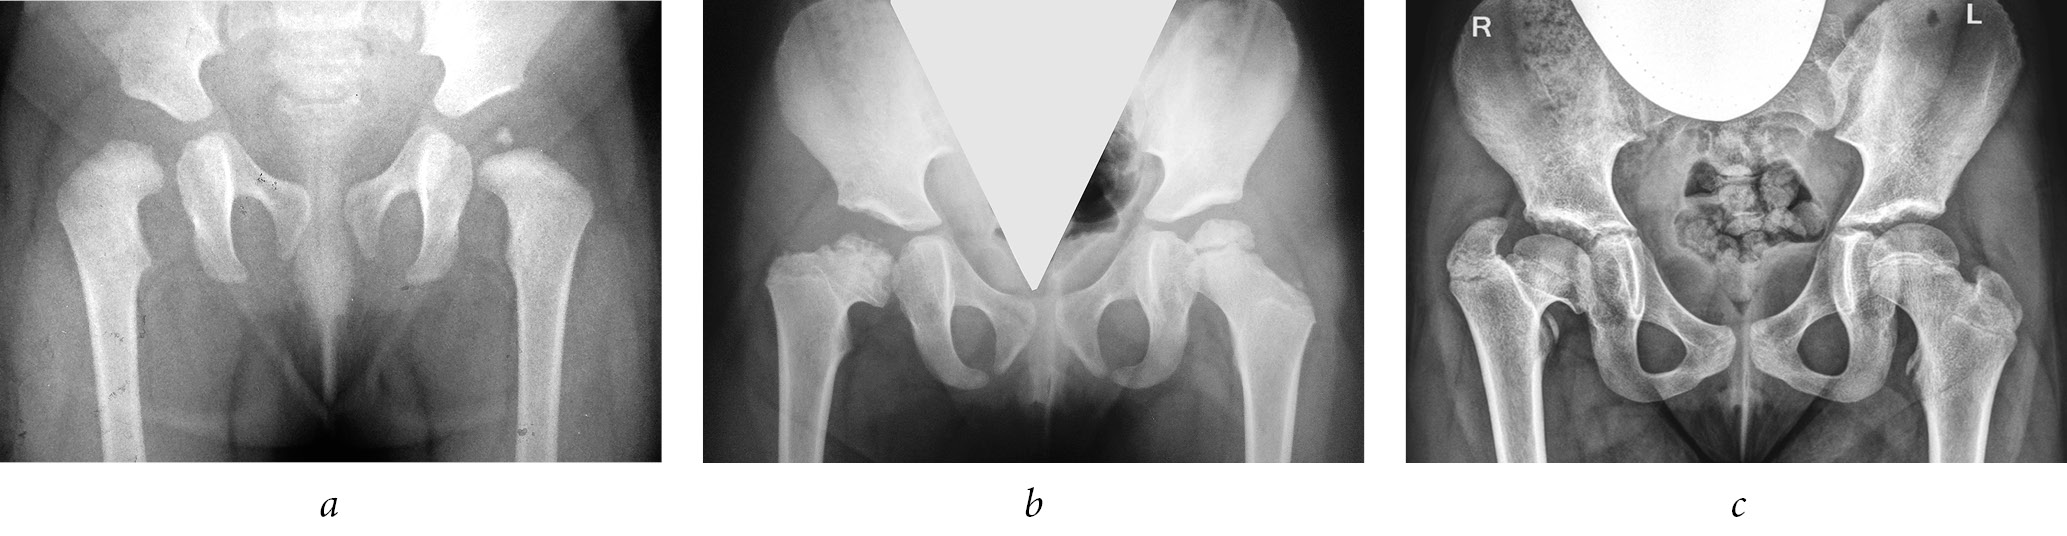

- consequences of the femoral head ischemic necrosis as a complication of conservative treatment for hip dysplasia and congenital dislocation of the hip in 143 (40.9%) of all the patients (Fig. 3);

Fig. 3. Radiographs of patient Sh. at the ages of 1 year, 2 months (a), 3 years, 9 months (b), and 11 years (c). Formation of multiplanar deformity of the proximal femur with a high position of the greater trochanter after avascular necrosis of the femoral head (on the right, Kalamchi and MacEwen class IV; on the left, Kalamchi and MacEwen class II). The patient had a history of conservative treatment for congenital bilateral dislocation of the hip